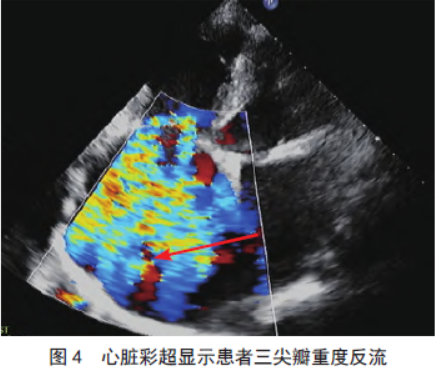

心脏彩超(图2-4)示:双房扩大、主动脉窦部增宽、升主动脉扩张、肺动脉扩张、主动脉瓣退行性改变伴轻度反流、二尖瓣狭窄

伴二尖瓣重度反流(二尖瓣最大开放径12 mm,解剖面积0.98 cm2)、三尖瓣重度反流、肺动脉高压、左房压增高。未吸氧时测动脉血气:pH 7.38,血二氧化碳分压54 mmHg,血氧分压32 mmHg,碱剩余

6.8 mmol/L;经鼻吸氧(氧浓度37%)2 h 后所测的动脉血气:pH7.48,血二氧化碳分压39 mmHg,血氧分压108 mmHg,碱剩余5.5 mmol/L。评估代谢当量为4,心功能Ⅲ级,美国麻醉医师协会分级Ⅲ级。